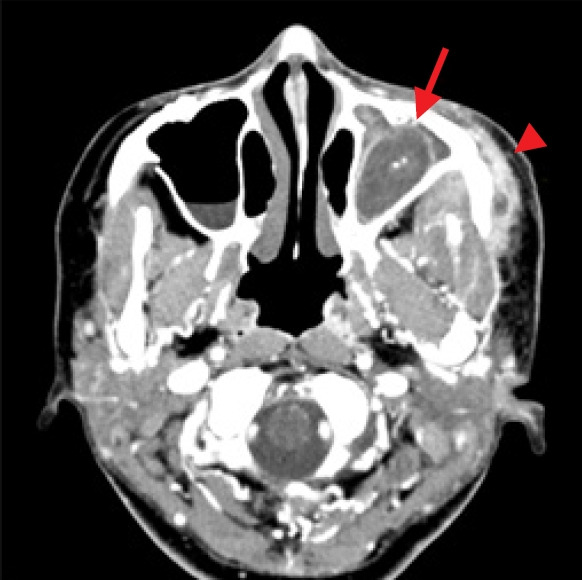

本病例报告描述了我们对一名 35 岁女性顽固性肛周脓肿的治疗。脓肿是在颧骨缩小手术后形成的,在手术过程中,术前存在的真菌球没有得到处理。我们的综合治疗方法包括功能性内窥镜鼻窦手术、真菌球摘除、脓肿引流和清创。术后两周,患者症状缓解。术后 6 个月的随访没有发现复发或并发症的迹象,患者对功能和美观效果均表示满意。该病例强调了彻底术前评估的重要性,并提高了人们对无症状病变未经治疗的潜在风险的认识,因为这些病变可能会发展并导致进一步的并发症。

This case report describes our treatment of a persistent periantral abscess in a 35-year-old woman. The abscess developed following a zygoma-reduction surgery, during which a preexisting fungal ball had not been addressed. Our comprehensive treatment approach included functional endoscopic sinus surgery, fungal ball removal, abscess drainage, and debridement. Two weeks postoperatively, the patient's symptoms had resolved. A 6-month postoperative follow-up revealed no signs of recurrence or complications, and the patient reported satisfactory functional and aesthetic results. This case underscores the importance of thorough preoperative evaluations and raises awareness about the potential risks of untreated asymptomatic pathologies, which can potentially progress and lead to further complications.